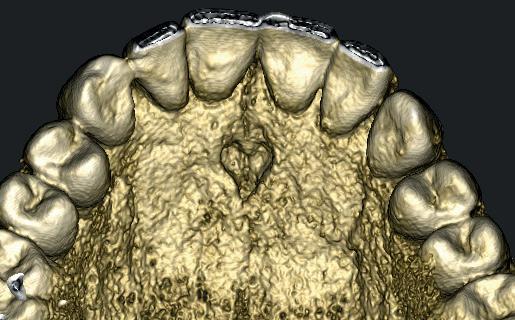

Hij heeft een CBCT-scan gemaakt en na extractie de 13 vervangen door een implantaat. Er was nog wat onduidelijkheid over de status van de 11, dus we hebben hem expliciet laten kijken naar het vermeende resorptiedefect. Dit bleek echter een groot foramen incisivum, dus een overprojectie, zelfs in de vorm van een hartje (afbeelding 19, met dank aan Irfan Abas).